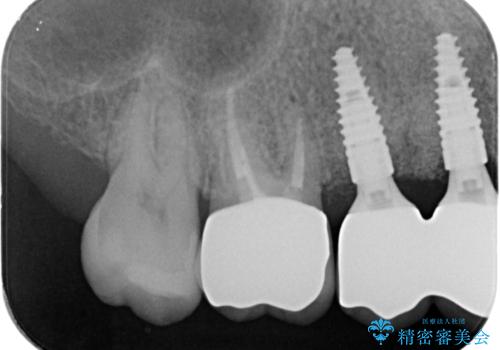

- 176万円(インプラント×4・チタンカスタムアバットメント×4・ジルコニアクラウン×4・仮歯×4)費用は治療当時の料金となります

見た目が白くなり喜んでいただけただけでなく、しっかりとした噛めるようになり食事を不安なく楽しんでいただけるようになりました。